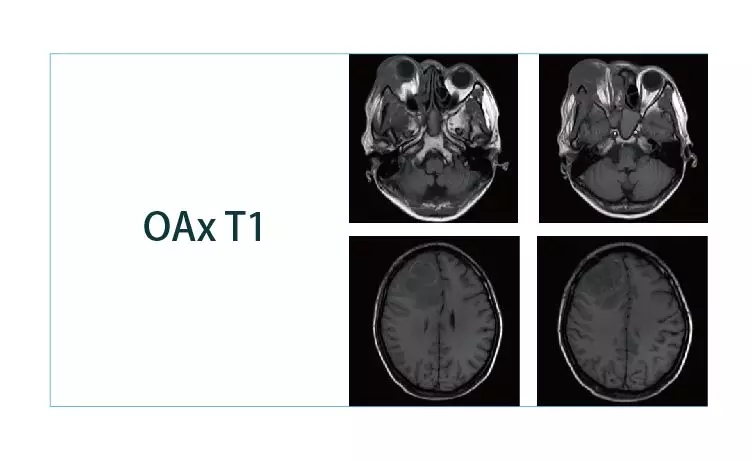

【朗润影像档案】20190118磁共振影像病例结果讨论